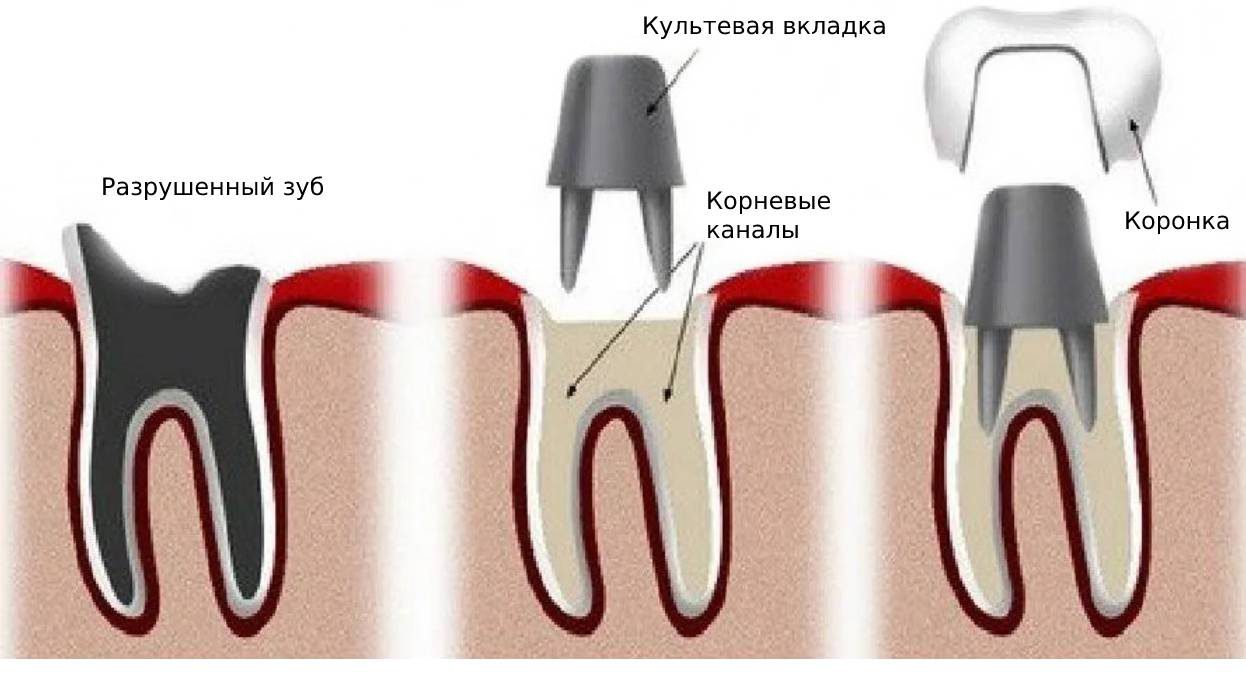

Культя зуба это

Культя зуба это 106 фото